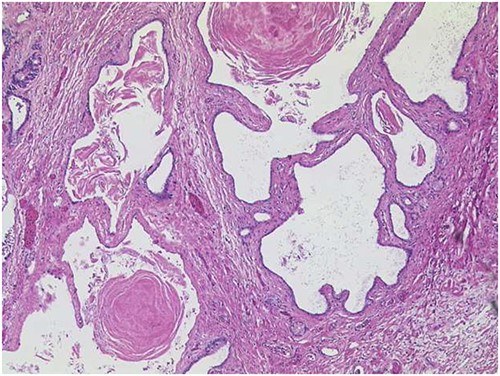

Histopathological examination of the pancreatic specimen showed a pronounced lymphoplasma cellular inflammation and was considered to be a chronic atrophic pancreatitis with no evidence of malignancy. Further histological cross-sections showed that the lesion was composed of multilocular cysts in the entire pancreas measuring up to 1.1 cm, shown in Fig. 3. Microscopically, the cysts were aligned by epithelium with regions of either acinar shown in Fig. 4 or ductal differentiation shown in Fig. 5, without nuclear atypia or mitoses. The surrounding parenchyma was atrophic and fibrotic. Immunohistochemical stains confirm the distinct regions of acinar differentiation (positive for BCL10, trypsin and chymotrypsin) shown in Fig. 4(B–D) and those of ductal differentiation (negative for BCL10, trypsin and chymotrypsin) shown in Fig. 5(B–D), leading to the final diagnosis of ACT.

ACT of the pancreas with cysts of varying sizes, surrounded by fibrotic pancreatic parenchyma (HE ×50). On cross-section, the lesion is composed of multilocular cysts in the entire pancreas, measuring up to 1.1 cm.